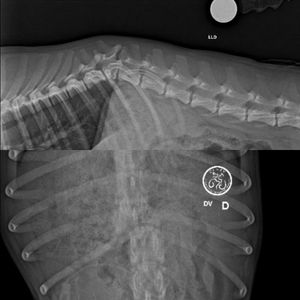

Leão foi encontrado atropelado na beira de uma BR em Rondonópolis/MT. Ele teve uma luxação na coluna e precisa muito operar. A cirurgia ficou no valor de R$5 mil reais, não incluso internação (R$890) e medicações. Pedimos de coração o apoio de vocês para ajudar nosso menino a fazer essa cirurgia e para ele ter melhor qualidade de vida. Contamos com vocês! ❤️